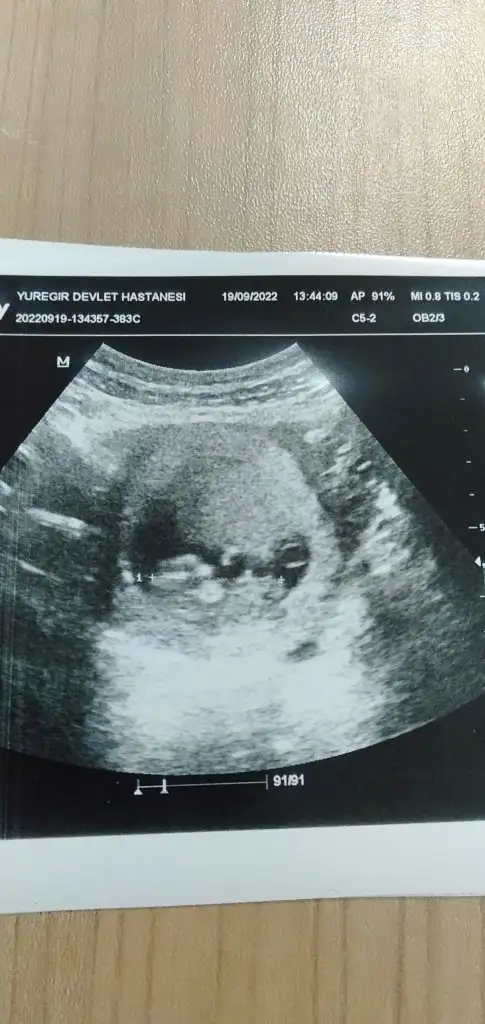

Kız değil mi14 haftalık bende tahmin alablrmiyim

Doktor daha belli değil dedi banada kız gbi geldi de öğrenemedm dahaKız değil mi

Daha belli değilse kızdır bide bacak arası boşDoktor daha belli değil dedi banada kız gbi geldi de öğrenemedm daha

12 haftalık benimkini de yorumlar mısınızRamzi teorisine göre cinsiyet tahmini yapabilir misiniz?

Vajinal ultrasonla bakıldı 7+5 haftalıkŞimdiden teşekkürler